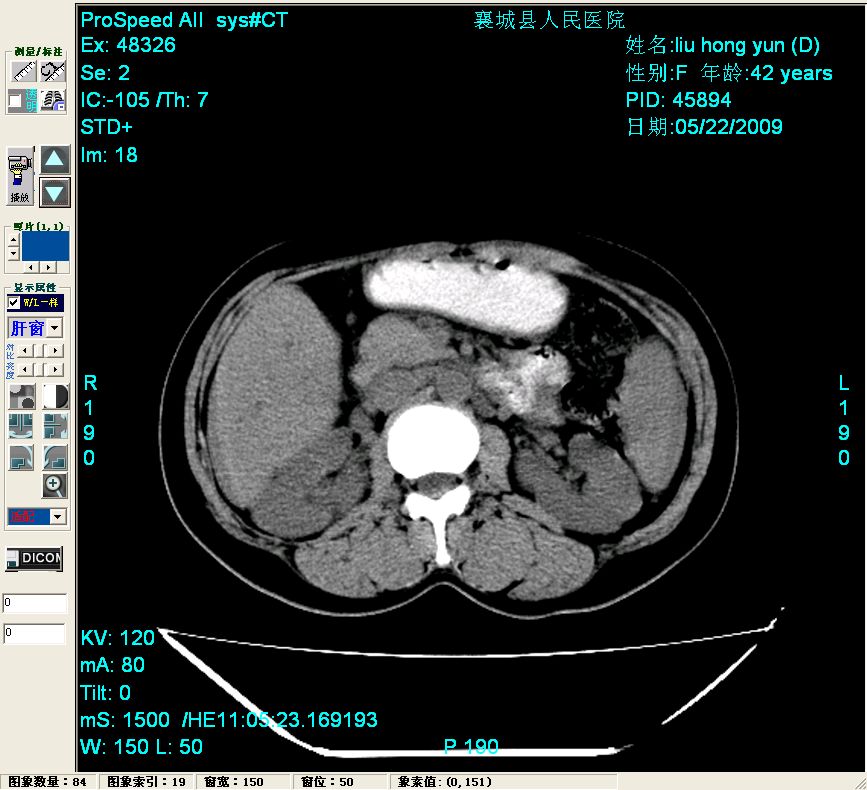

增强:

胰头部见结节状高密度影,其前方略可分辨扩强胆部管,平扫到增强始终有,但现在尚难与胃肠造影剂鉴别.

结合病史考虑,1现在引起黄疸体征的原因应该是胆总管胰段结石阻塞,建议局部胃肠造影剂排空后复查.

胆总管末端结石伴肝内胆管扩张合并结石!另:不除外合并胆系感染!

考虑:1、胆道结石伴肝内胆管扩张、积气;胆系感染!2、从平扫、增强片来看,不存在胆管肿瘤征象;3、提介建议:作为影像医师,在做一项检查之前应先熟悉临床医生的目的,象这个病例,检查前就不应喝高密度造影剂,而应充分喝好水就可,要不适得其反,反而较难判断胆总管下段是否有结石。